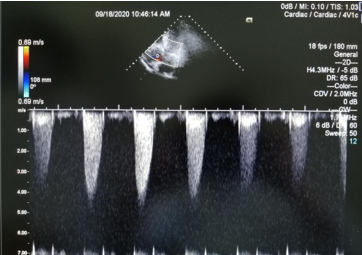

心脏杂音是由于心腔或大血管内的血液流动紊乱形成旋涡,使心室壁、心瓣膜或血管壁发生震动而产生,也可以是由于血流经过心腔或心瓣膜时速度增快而产生。心脏杂音一般可分为两类:一类是生理性或功能性杂音,轻而柔和,多发生于正常青年人,也见于发热、贫血、情绪激动、运动后及有甲状腺功能亢进症的患者;另一类是病理性或器质性杂音,可见于先天性心脏病、冠心病、风湿性心脏病、心肌病等各类心脏病。对有病理性杂音者要格外引起重视,需要行心脏彩超等检查进一步明确诊断。该患者经心脏彩超检查确诊为主动脉瓣二瓣畸形、主动脉瓣重度狭窄合并轻度关闭不全。

提示主动脉瓣重度狭窄